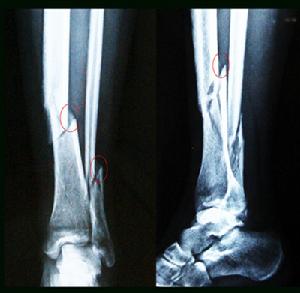

閉合性骨折的X線檢查X線檢查對閉合性骨折的診斷和治療具有重要價值。凡疑為閉合性骨折者應常規進行X線拍片檢查,可以顯示臨床上難以發現的不完全性閉合性骨折,深部的閉合性骨折、關節內閉合性骨折和小的撕脫性閉合性骨折等。即使臨床上已表現為明顯閉合性骨折者,X線拍片檢查也是必要的,可以幫助了解閉合性骨折的類型和閉合性骨折端移位的情況,對於閉合性骨折的治療具有重要指導意義。

閉合性骨折的X線檢查一般應拍攝包括臨近一個關節在內的正、側位片,必要時並拍攝特殊位置的X線片,如掌骨和跖骨拍正位及斜位片,跟骨拍側位和軸心位,腕舟狀骨拍正位和蹀位,有時不遺確定損傷情況時,尚需拍對側肢體相應部位的X線片,以便進行對比,值得注意的是,有些輕微的裂縫閉合性骨折,急診派片未見明顯閉合性骨折線如臨床症狀較明顯者,應於傷後2周拍片複查,此時,閉合性骨折端的吸收常可出現閉合性骨折線,如腕舟骨閉合性骨折。